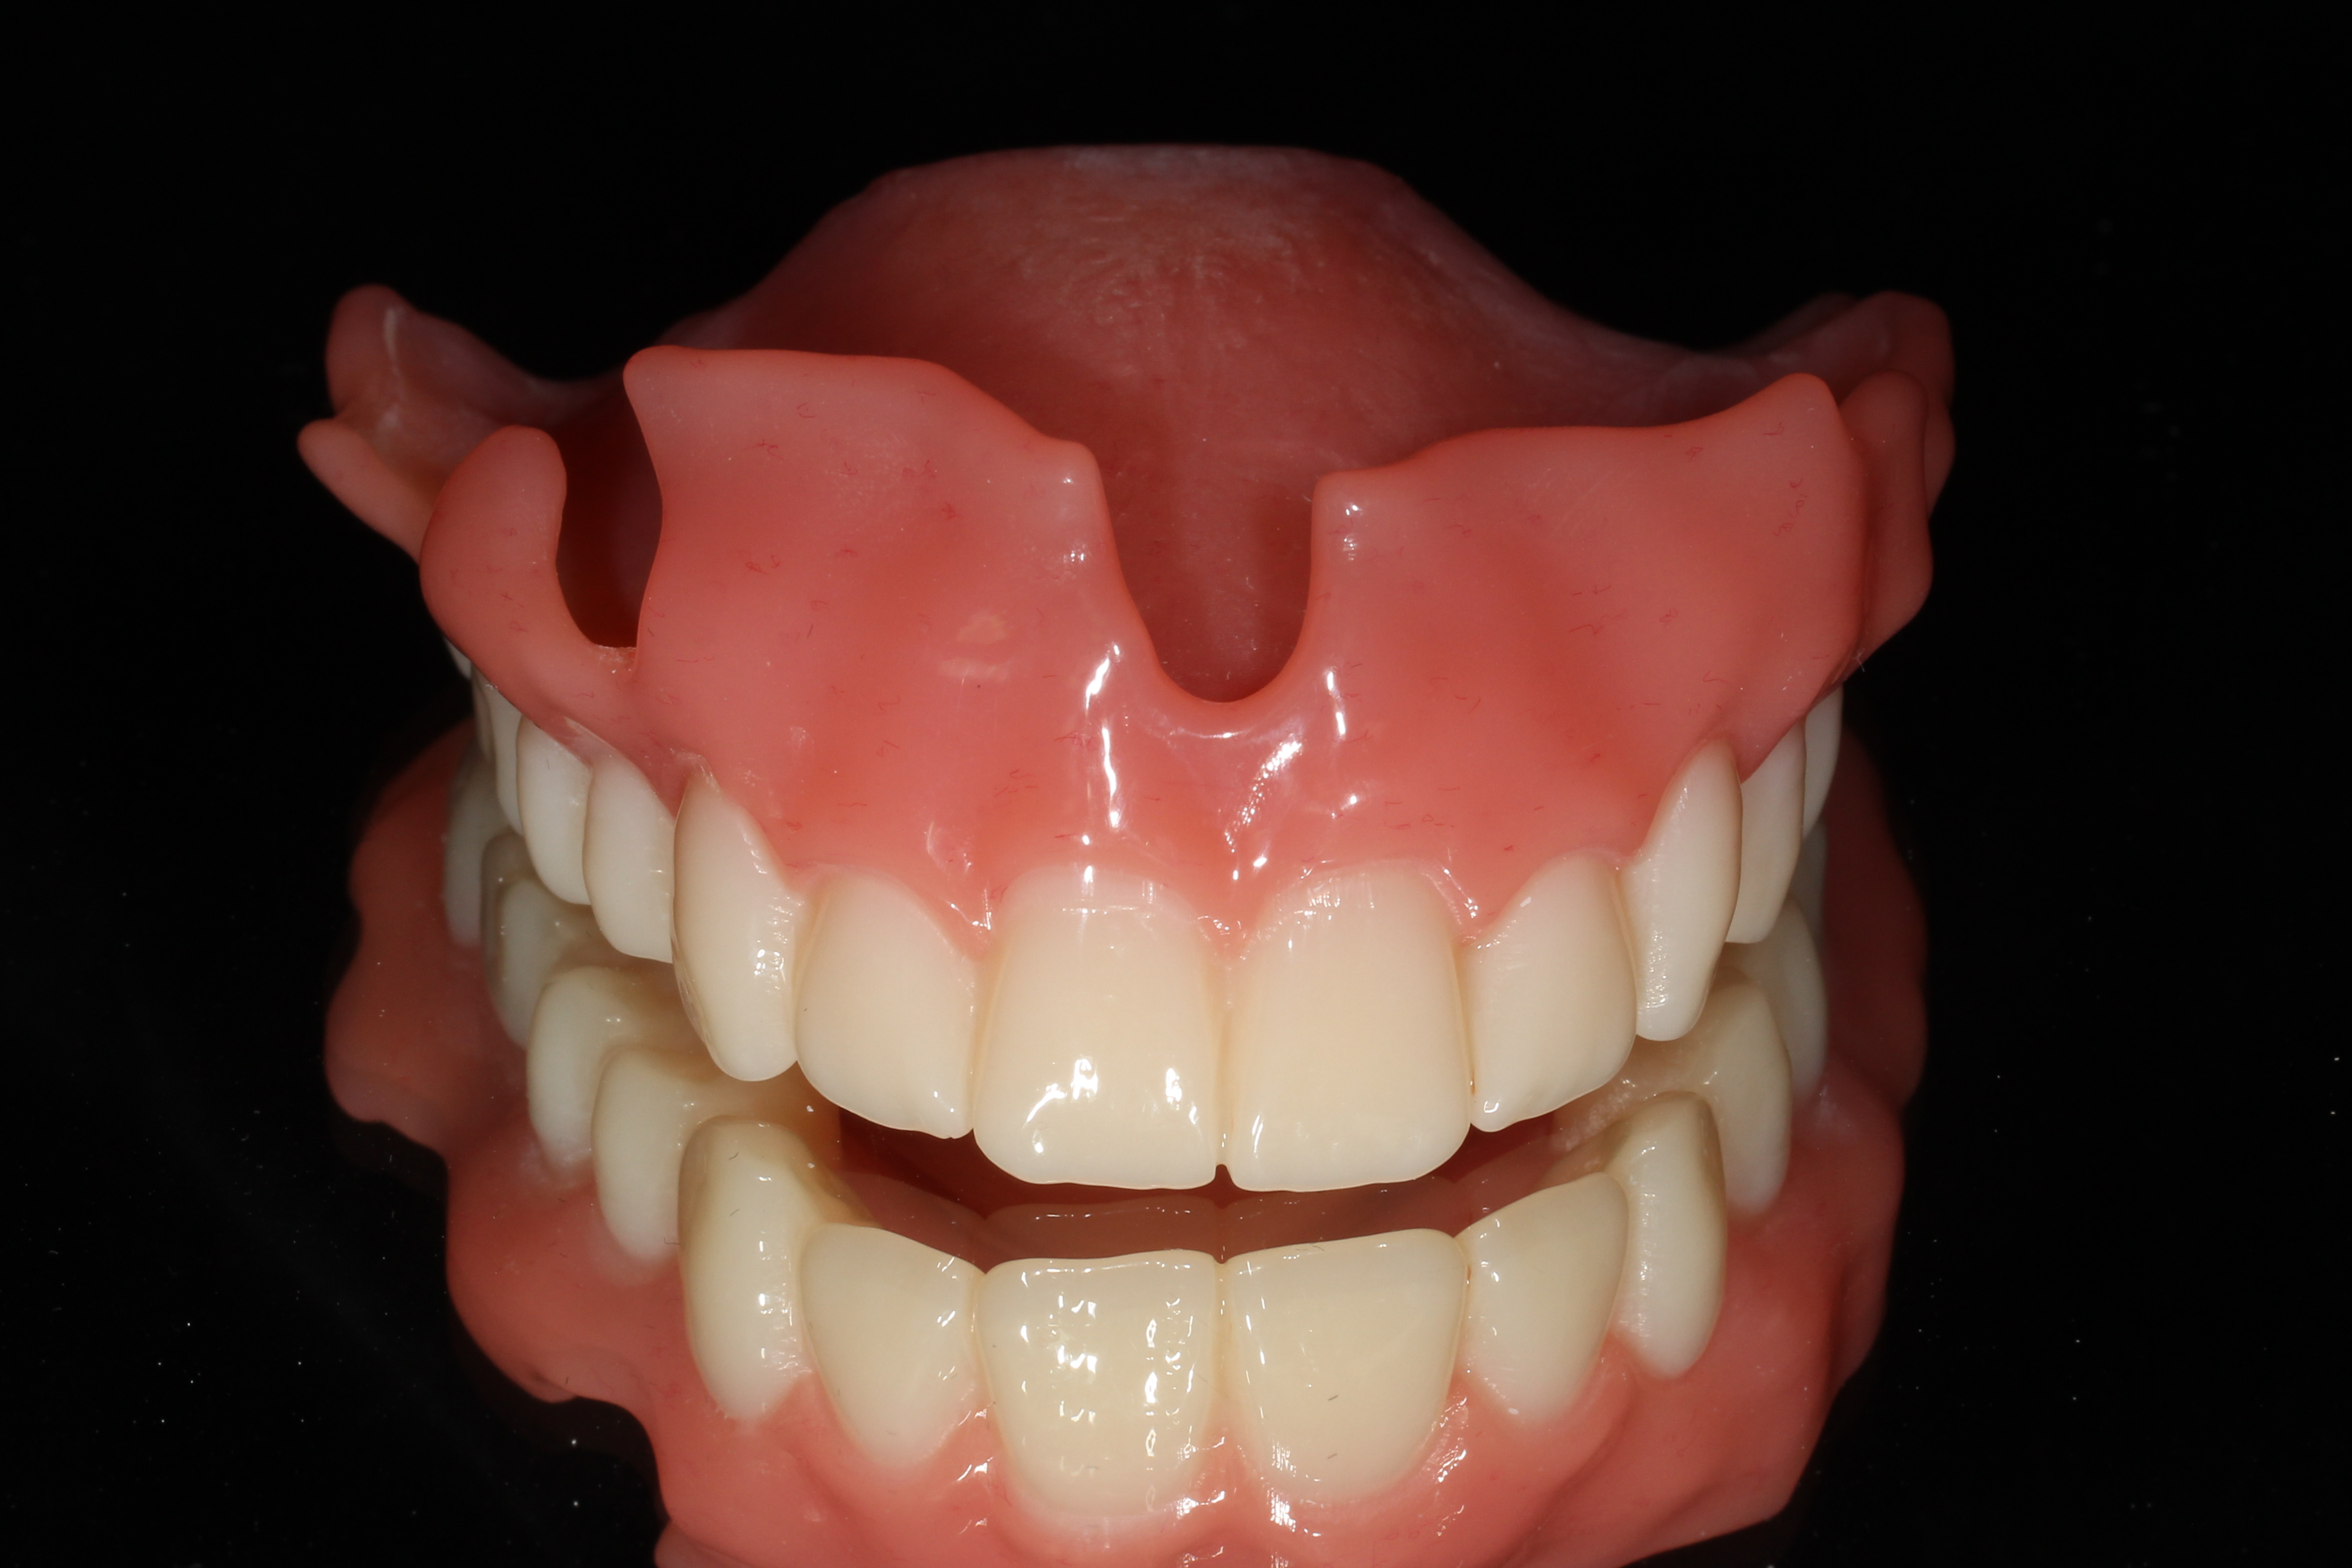

螺絲固持式假牙 「螺絲固持式假牙」,簡單說,就是運用生物性相容的螺絲,來將口內的植體拴緊,並且是可拆卸的。客製化人工支台齒及牙冠透過螺絲來固定,方便醫師日後可將假牙拆卸進行清潔保養,避免發炎並延長植牙壽命。「螺絲固持式假牙」:專業的贋復科醫師會依據病患者口腔的情況,製作客製化的支台齒與牙冠,而假牙運用螺絲固定在植體,同時運用可以拆卸的方式,固定在人工牙根上,由於是可拆式的,所以醫師會在牙齒的顎側面或者咬合面,設置一個維修的開口。由於螺絲固持式假牙是可拆卸的,因此病患必須3-6個月進行回診與追蹤,讓專業的贋復科醫師將假牙拆下,不僅要將植體周為進行清潔,也必須將假牙清潔乾淨,才能降低植體周圍炎產生的機率,同時增加植牙的使用年限。 黏著式假牙 「黏著式假牙」,簡單說,就是使用生物相容性的黏劑,將植牙的牙套黏在支台齒上。雖然「黏著式假牙」製作與設計上比較簡單,但是必須使用黏著劑來輔助,來固定假牙的位置,因為病患長期使用會出現,黏膠流失、假牙鬆脫的情形。「黏著式假牙」最大的問題,在於黏著時溢出的黏著劑不易清潔,殘留的黏劑會不斷刺激牙肉的周圍,導致植體周圍炎的發生,植體周圍骨頭流失。「黏著式假牙」不可拆卸的問題,會導致口腔健康維護不易,醫師無法輕易取下假牙保養植體,增加口腔內植體病變的風險。 黏著式假牙VS螺絲固持式假牙 「螺絲固持式假牙」:使用生物性相容的螺絲,來將口內的植體拴緊,並且是可拆卸的。「黏著式假牙」:使用生物相容性的黏劑,將植牙的牙套黏在支台齒上。「黏著式假牙」的黏著劑如果使用不當,不僅在取下的過程中難度相當高,大部分的時候,都必須要完全破壞牙冠,才能完全取下,而且過程中必須藉由醫師經驗與技術,降低病患的不適感。這也會導致病患必須多花一筆費用,重新製作假牙。而且殘留的黏劑會不斷刺激牙肉的周圍,導致植體周圍炎的發生,植體周圍骨頭流失。「螺絲固持式假牙」是人工支台齒及牙冠透過螺絲來固定,而且牙齒的顎面或者咬合面有個維修洞,所以拆卸來的過程相當容易。也因為「黏著式假牙」不容易拆下,所以植體周圍炎發生的機率會比「螺絲固持式假牙」還要高出許多。 - 幾歲植牙比較好? 2026.01.19